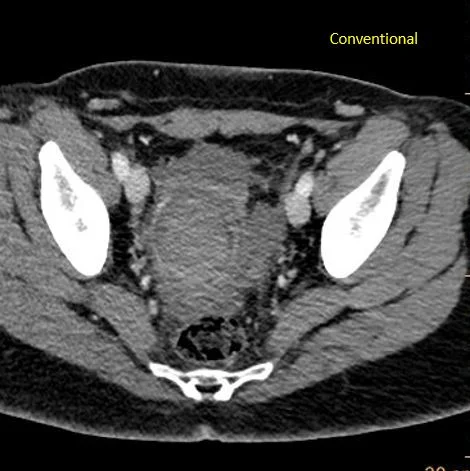

Conventional CT: Just a big mess in the pelvis.